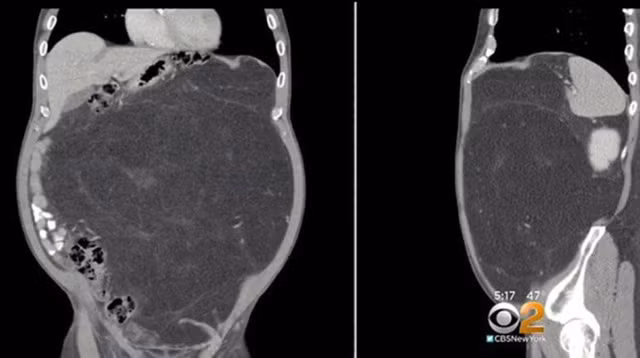

Sau khi chụp chiếu, các bác sĩ cũng phát hoảng khi tìm thấy khối u trong bụng Kevin, một khối u có kích thước khổng lồ. Chẩn đoán ban đầu cho thấy người đàn ông mắc bệnh u mỡ ác tính và nếu không phẫu thuật kịp thời, rất có thể Kevin sẽ gặp nguy hiểm tới tính mạng.

Trong quá trình phẫu thuật, các bác sĩ còn sốc hơn gấp bội khi loại bỏ được khối u lớn gấp 3 lần kích thước chẩn đoán ban đầu. Khối u còn lớn tới mức bắt đầu di chuyển vào trong nội tạng và quấn quanh một quả thận của Kevin.